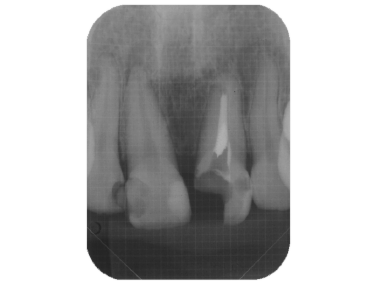

- 前歯の違和感を主訴に来院した症例(写真をクリックして下さい)

- 歯内療法の不備から上顎洞にまで炎症が波及してしまった症例

初診時のレントゲン写真

写真の右から2本目の歯の違和感でいらっしゃいました。

CT撮影すると、炎症は上顎洞にも波及しています

このように、通常のレントゲンだけでは炎症による病変の範囲等がわかり難い場合はCT撮影も行います。